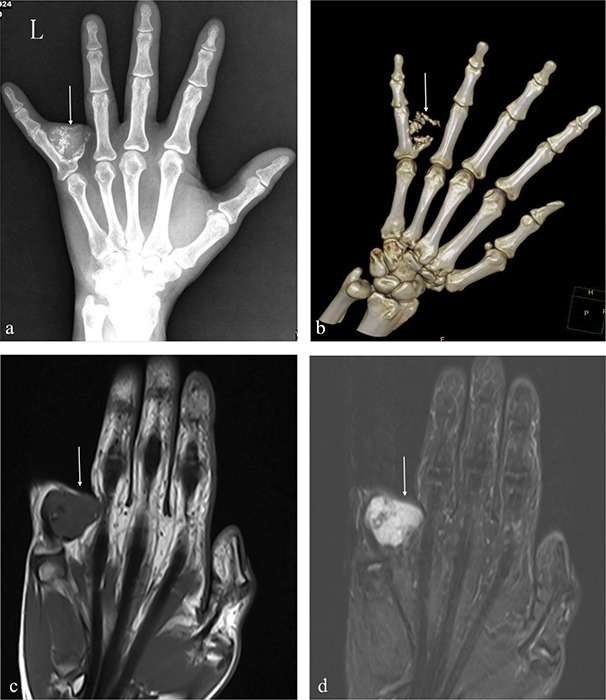

教学要点:骨膜软骨瘤是一种罕见的软骨瘤类型,其特征是骨膜下,钙化的软组织肿块压迫皮质骨,不累及髓腔。

Teaching point: Periosteal chondroma is a rare type of chondroma characterized by a subperiosteal, calcified soft tissue mass that compresses the cortical bone and does not involve the medullary cavity.